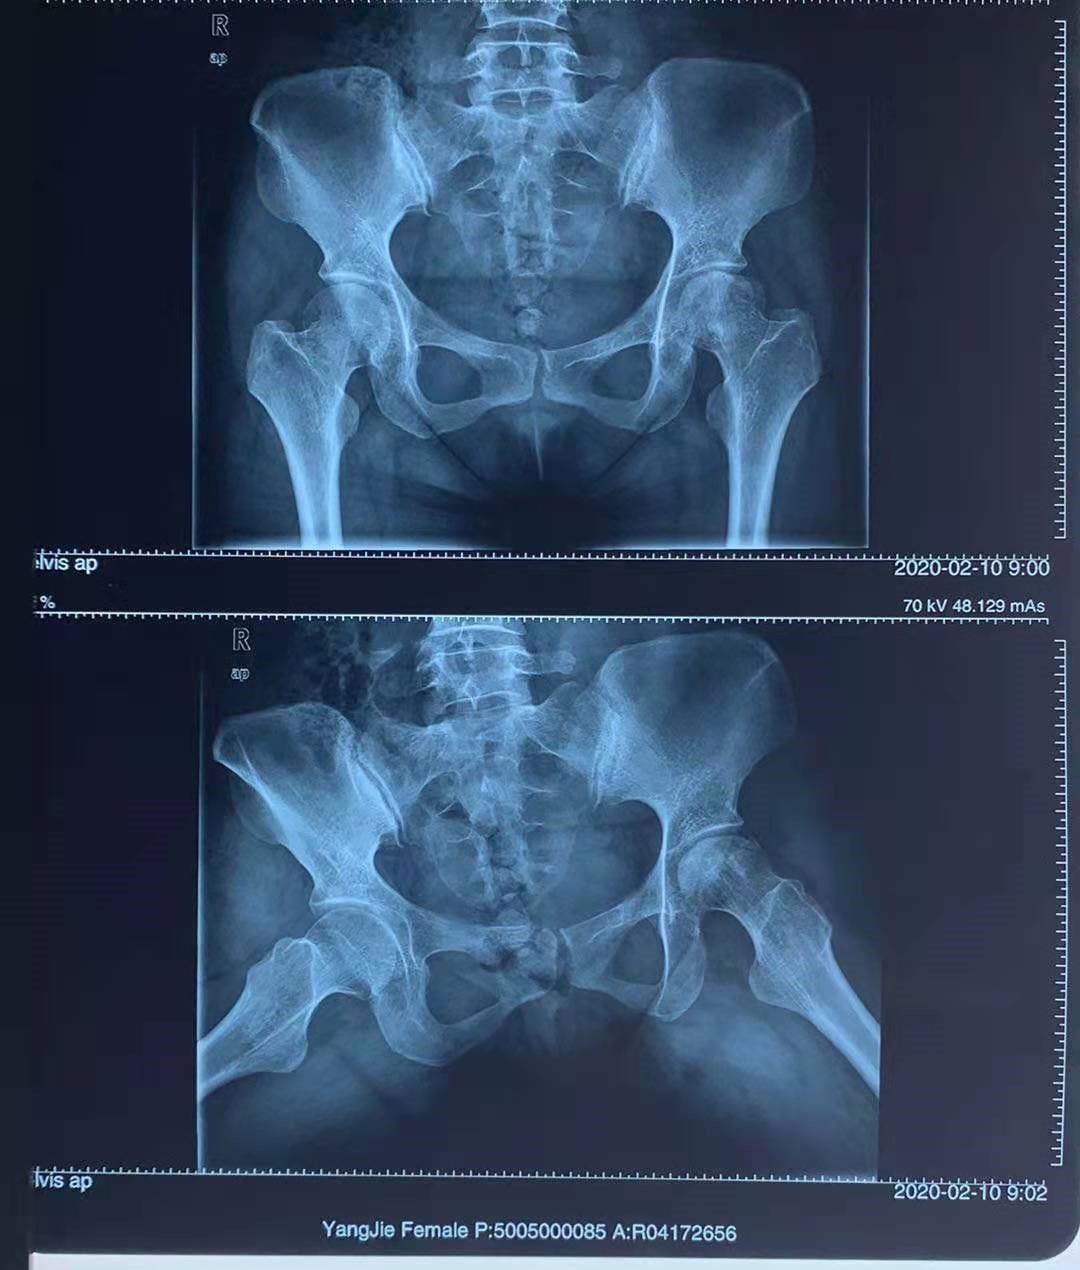

双侧股骨头坏死,右侧II期,左侧III期(已塌陷)